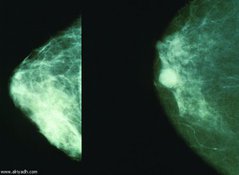

![]() В британском, и не только, обществе уже давно идут дебаты вокруг оправданности обязательного массового скрининга женской части населения на рак молочной железы.

У части специалистов вызывает сомнение как эффективность этого метода для раннего выявления заболевания, так и соблюдение баланса между приносимой им пользой и вредом для здоровья. Последнее исследование ученых из Оксфорда может склонить чашу весов в сторону "маммо-скептиков" и заставить многих британок еще тщательнее взвесить все "за" и "против", прежде, чем отправиться на процедуру. Открытое письмо главному онкологуВот уже четверть века, с 1988 года, в Великобритании действует программа Национальной службы здравоохранения (NHS) по выявлению рака груди у женщин в возрасте от 50 до 64 лет. Британкам из этой возрастной группы их семейные врачи регулярно настоятельно напоминают о необходимости сделать маммографию. Однако все эти годы в стране не утихают споры вокруг этой программы, особенно обострившиеся в последние несколько лет. Так, осенью 2011 года Сьюзан Бьюли, профессор в области акушерства и гинекологии из лондонского Королевского колледжа, написала открытое письмо главному британскому онкологу, сэру Майку Ричардсу, в котором сообщила о своем решении отказаться от регулярных обследований, несмотря на семейную историю рака груди, в связи с высоким процентом избыточной диагностики и обвинила NHS в сокрытии всей правды о маммографии. В ответ Ричардс пообещал способствовать проведению независимых исследований относительно пользы и вреда массового скрининга. Эти независимые исследования, о результатах которых стало известно через год, осенью 2012 года, показали, что регулярные обследования на 20 процентов снизили смертность от рака груди у их участниц, ежегодно спасая около 1300-1400 жизней. И другая сторона медалиОднако была выявлена и другая статистика — около 4 тысяч британок ежегодно по итогам маммографического исследования подвергаются совершенно не нужному им лечению, включая мастэктомию, лучевую и химиотерапию. Таковы тяжелые, зачастую разрушающие жизнь последствия той самой избыточной диагностики, о которой говорила Бьюли — обнаруженные во время маммографии изменения в тканях молочной железы были столь незначительны и прогноз их злокачественного перерождения и быстрого роста был столь невелик, что, не будь обследования, они не принесли бы женщинам за всю их жизнь никакого вреда. Узнав об этой двоякой статистике — на каждую спасенную жизнь приходится три разрушенных — Ричардс распорядился пересмотреть правила проведения программы массового скрининга, отменив обязательность участия в ней и предоставив женщинам самим решать, взвесив все за и против, обследоваться им или нет. Вопреки ожиданиямМежду тем результаты масштабного анализа, проведенного специалистами Оксфордского университета, поставили под сомнение и первую часть исследований 2012 года — положительное влияние массовых маммографических обследований на уровень смертности от рака молочной железы. В рамках своей работы, опубликованной в июньском выпуске журнала Journal of the Royal Society of Medicine, авторы изучили статистические данные о смертности в регионе Оксфорда с 1979 по 2009 год, а также данные о смертности от рака груди по всей Великобритании во всех возрастных группах с 1971 по 2009 год, то есть почти за сорок лет. Регион Оксфорда был выбран потому, что только в нем, в отличие от остальной страны, в свидетельстве о смерти указываются все возможные причины смерти. Особое внимание ученые обращали на положение со смертностью от рака груди до и после 1988 года. Вопреки ожиданиям, наибольшие снижение показателей смертности было выявлено не в возрастной группе 50-64 года, а среди женщин моложе 40 лет, которые не проходят регулярного обследования. Так, в период с 1988 по 2001 в этой возрастной группе было отмечено снижение уровня смертности на два процента, а в период с 2001 по 2009 год — на пять процентов. А вот на смертность женщин в возрасте 50 — 64 лет, как отмечают авторы, рутинное тестирование на рак груди, в сравнении с более молодой группой, практически не повлияло — в первый из временных периодов их показатель упал лишь на 1,2 процента, а во второй — на три процента. Статистика свидетельствует о том, делают вывод авторы, что хотя в каждом отдельном случае обследование может принести пользу, на популяционном уровне эффекта от массового скрининга на рак молочной железы, который, как ожидалось, должен был значительно снизить смертность от этого заболевания, не наблюдается, а общее снижение этого показателя связано с качественным улучшением методов терапии. Словом, решение об участии в программе или отказе от него стало для британок еще более трудным, чем прежде. Александр Орлов |